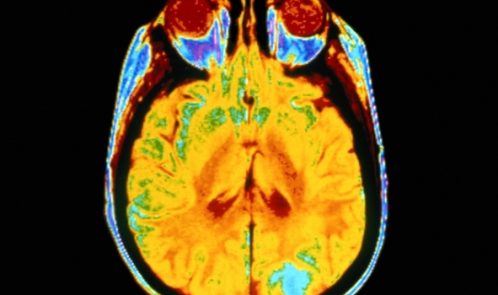

در روش UCLA محققین از یک ابزار آزمایشی استفاده نمودند که حدودا به اندازه یک فنجان نعلبکی، برای تمرکز امواج اولتراسونیک بر روی تالاموس بود. ساختار تالاموس به شکل دو توده در اندازه گردو در مرکز مغز است که به عنوان کانون حیاتی برای جریان اطلاعات و کمک به تنظیم هوشیاری و خواب عمل می کند.

این مغز فعال شده متعلق به بردلی کرهان بود.